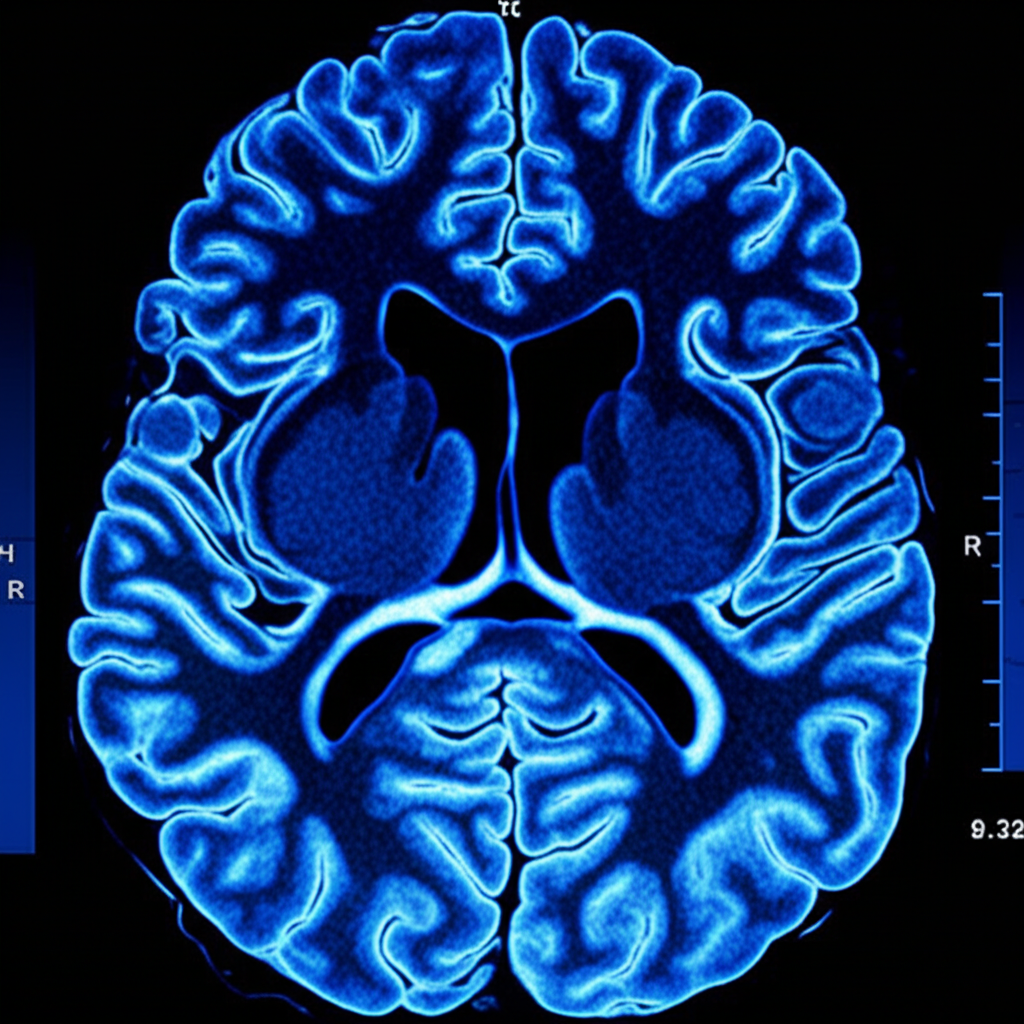

Assim como a tomografia e a ressonância transformaram o diagnóstico, a angiografia é hoje o padrão ouro para entender a anatomia vascular cerebral com precisão.